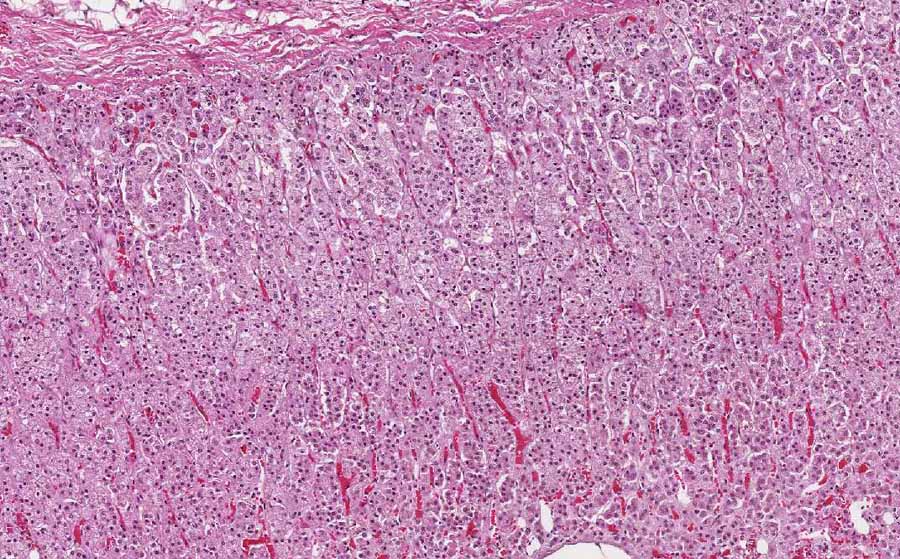

Area 1: Starting from the capsule, the adrenal cortex is composed of three layers or zones, namely the zona glomerulosa, zona fasciculata, and zona reticularis. The zona fasciculata is the thickest and comprises the bulk of what is being shown in this image. The cells are polygonal and monotonous. The nuclei are small, round, centrally located and the cytoplasm is foamy. Compare these cells with the tumor cells from Area 3.

Area 2: This is the interface between the tumor and the residual adrenal cells. Note that the residual cells around the tumor have more eosinophilic cytoplasm and are less foamy.

Area 3: The tumor has close resemblance to the residual adrenal cortex in terms of both histologic architecture and cytoplasmic features.

Gross Pathology: The tumor is 2.2 cm in greatest dimenstion. It is in the form of a single, well-demarcated nodule surrounded by a thin layer of normal appearing adrenal cortex. The tumor has a pale yellow, solid cut surface without any hemorrhage or necrosis. The residual adrenal cortex does not show any evidence of atrophy.

• The tumor (Area 3) is composed of solid sheets of monotonous, polygonal cells with foamy cytoplasm, distinct cytoplasmic membrane, and centrally located nuclei. There is no significant pleomorphism or enlargement of nuclei. No prominent nucleoli are noted. When compared to the normal cells of the residual adrenal cortex (Area 1), there are distinct similarities between the normal and neoplastic cells.